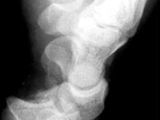

Absent Patella-Fongs

Absent Patella-Fongs